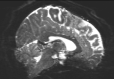

Refer to captionRefer to captionRefer to caption+vsubscript𝑣\mathcal{I}_{+v}inputRefer to captionRefer to captionRefer to captionPyHySCO (LBFGS)Refer to captionRefer to captionRefer to captionPyHySCO (GN)Refer to captionRefer to captionRefer to captionPyHySCO (ADMM)Refer to captionRefer to captionRefer to captionvsubscript𝑣\mathcal{I}_{-v}Refer to captionRefer to captionRefer to captionRefer to captionRefer to captionRefer to captionRefer to captionRefer to captionRefer to captionRefer to captionRefer to captionRefer to caption|+vv|subscript𝑣subscript𝑣|\mathcal{I}_{+v}-\mathcal{I}_{-v}|Refer to captionRefer to captionRefer to captionRefer to captionRefer to captionRefer to captionRefer to captionRefer to captionRefer to captionRefer to captionRefer to captionRefer to captionfield map 𝐛𝐛\mathbf{b}Refer to captionRefer to captionRefer to captionRefer to captionRefer to captionRefer to captionRefer to captionRefer to captionRefer to caption+vsubscript𝑣\mathcal{I}_{+v}TOPUPRefer to captionRefer to captionRefer to captionHySCORefer to captionRefer to captionRefer to captionvsubscript𝑣\mathcal{I}_{-v}Refer to captionRefer to captionRefer to captionRefer to captionRefer to captionRefer to caption|+vv|subscript𝑣subscript𝑣|\mathcal{I}_{+v}-\mathcal{I}_{-v}|Refer to captionRefer to captionRefer to captionRefer to captionRefer to captionRefer to captionfield map 𝐛𝐛\mathbf{b}Refer to captionRefer to captionRefer to caption